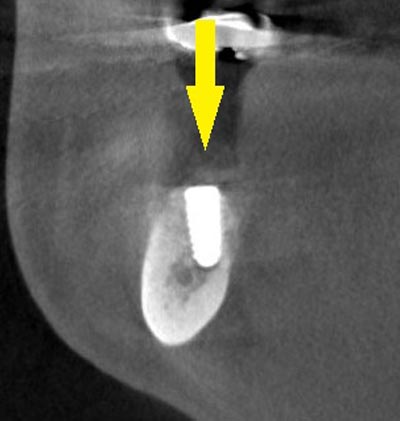

インプラント埋入後の、別な方向からみたCT画像です。神経の通る管にややギリギリでしたが、神経は傷つけずに、インプラントが埋入できました。この後、4か月ほどで、咬む歯の部分、上部構造を完成させました。

インプラント埋入後の、別な方向からみたCT画像です。神経の通る管にややギリギリでしたが、神経は傷つけずに、インプラントが埋入できました。この後、4か月ほどで、咬む歯の部分、上部構造を完成させました。